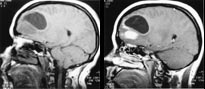

Svulster kan opptre i alle aldre og med høyst forskjellig intrakranial lokalisasjon. Ved bruk av flere ulike pulssekvenser og snittplan kan MR fremstille en svulst bedre enn andre tilgjengelige metoder. MR er således bedre enn CT til å identifisere og nøyaktig lokalisere svulsten. Samtidig forbedres fremstillingen av tumormorfologien, effekten på omkringliggende hjernevev og store intrakraniale blodkar. MR identifiserer solide og cystiske tumorkomponenter så vel som kontrastmiddeloppladende eller ikke-oppladende svulstvev (fig 1, 2 ). Ofte finner vi ved MR hjernemetastaser som ikke er synlige selv med en god CT-undersøkelse. Disse egenskapene ved MR har derfor kunnet gi vesentlig informasjon med henblikk på valg av terapi.